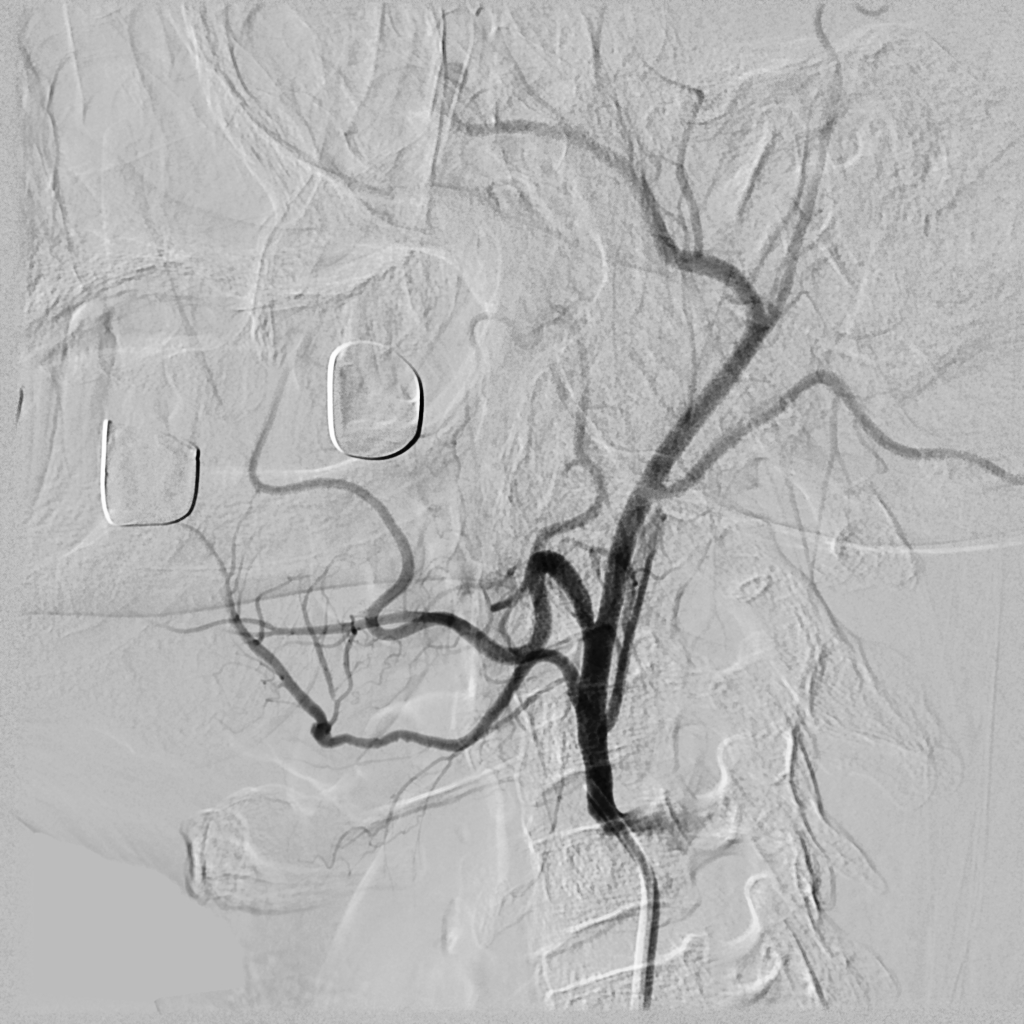

06.09.2011 был прооперирован пациент с опухолью языка с распадом, осложнившимся кровотечением. Внутрисосудисто, под местной анестезией пациенту была произведена селективная эмболизация язычной артерии и наружной сонной артерии. В послеоперационном периоде повторных эпизодов кровотечений не отмечено.

Селективная эмболизация артерий при опухолевых процессах позволяет предотвратить эпизоды кровотечений и уменьшить кровопотерю во время операций.